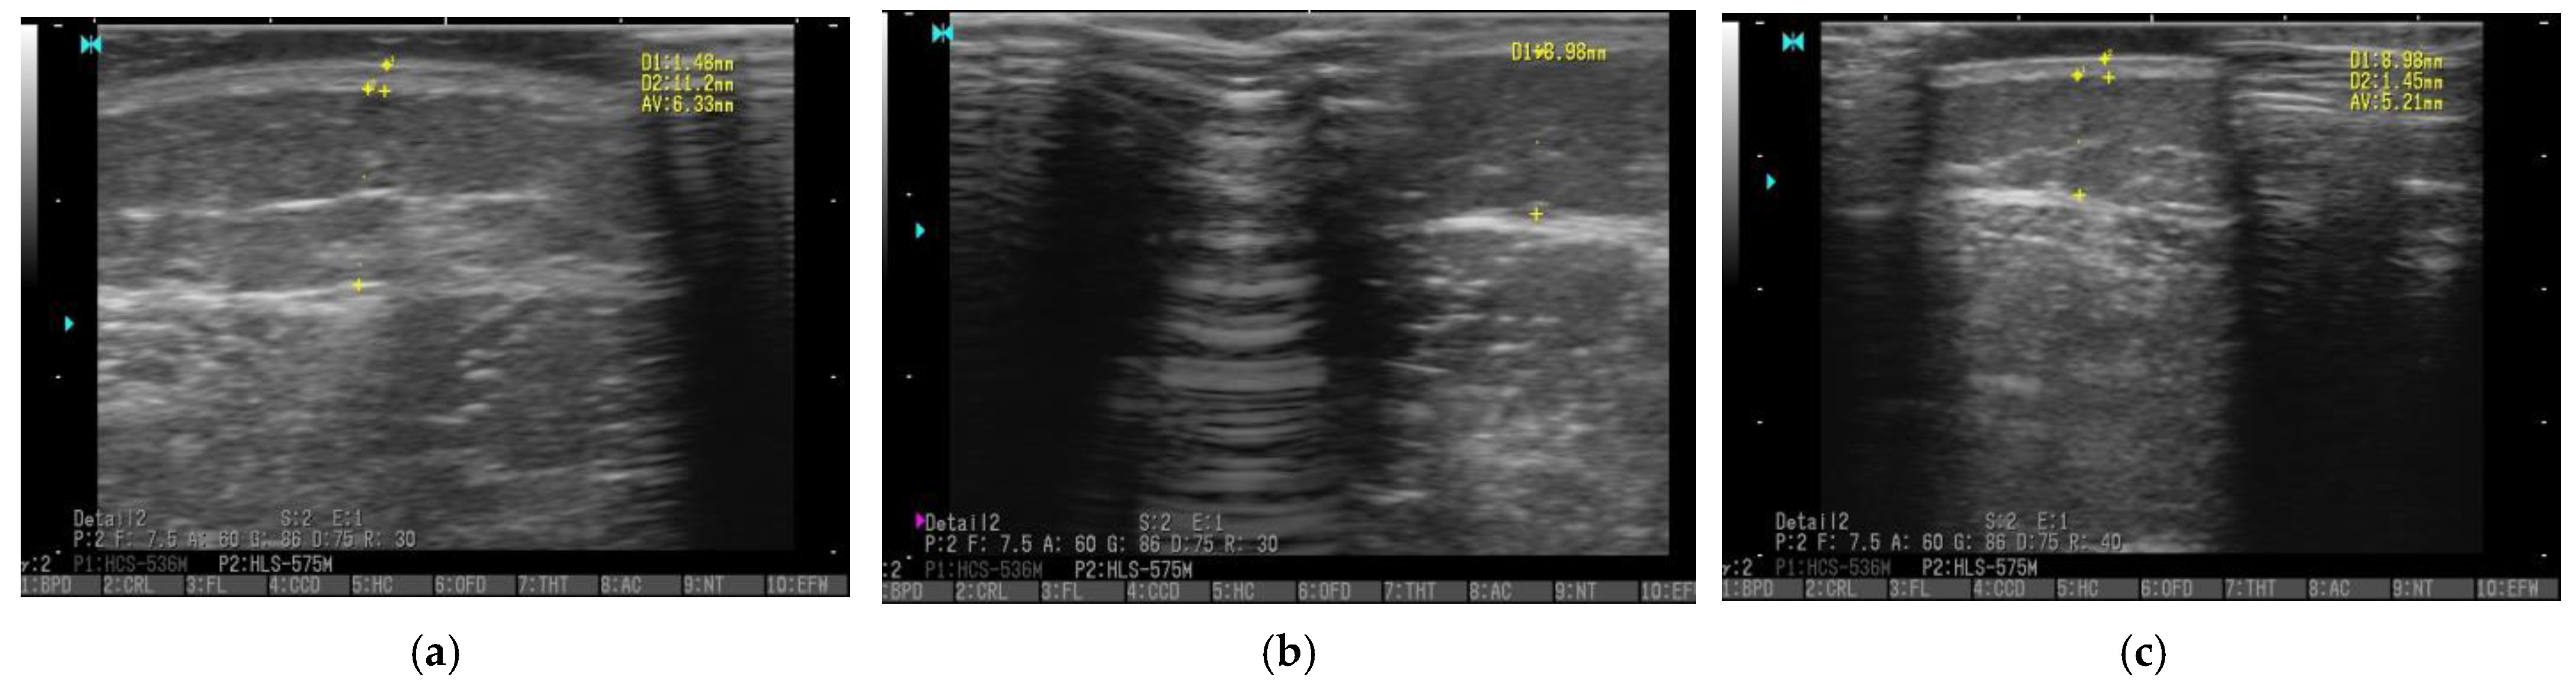

3.5. Ultrasonography

- Amato, A.C.M.; Saucedo, D.Z.; Santos, K.D.S.; Benitti, D.A. Ultrasound criteria for lipedema diagnosis. Phlebology 2021, 36, 651–658. [Google Scholar] [CrossRef] [PubMed]

- Hirsch, T.; Schleinitz, J.; Marshall, M.; Faerber, G. Is the differential diagnosis of lipoedema by means of high-resolution ultrasonography possible. Phlebologie 2018, 47, 182–187. [Google Scholar]